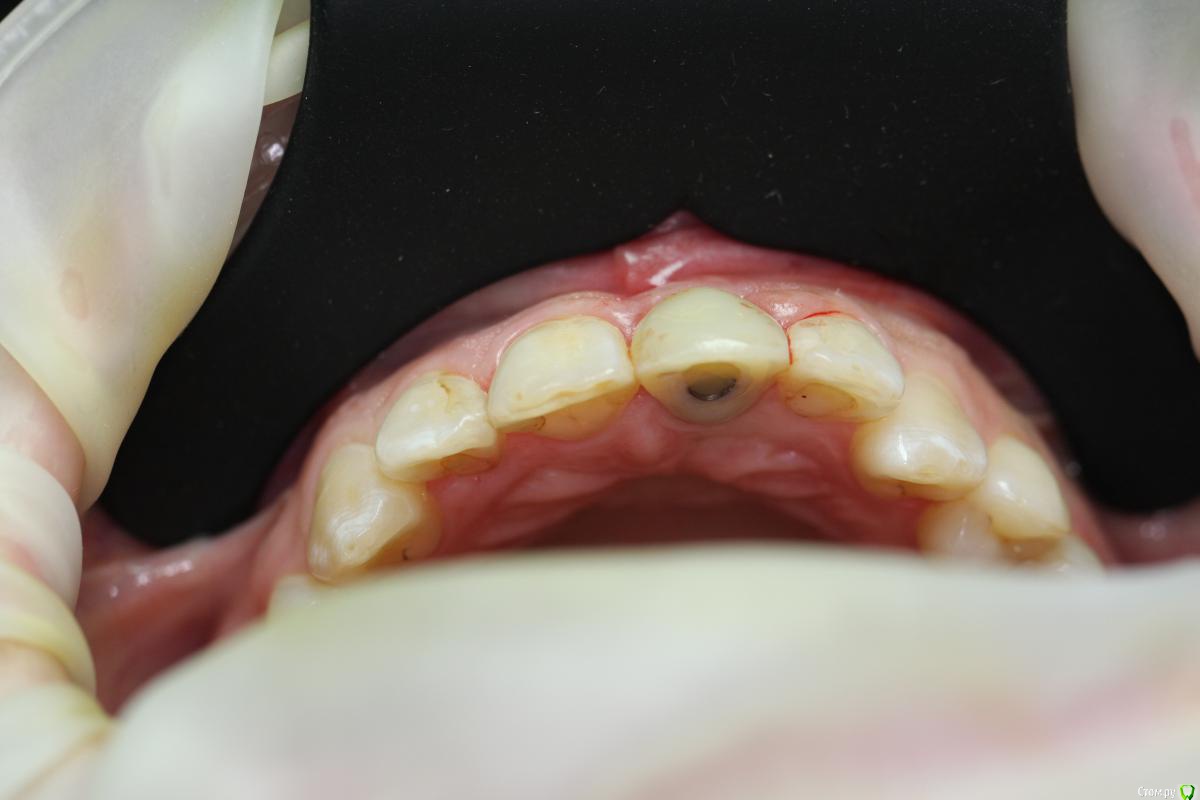

Zorrro Опубликовано 29 февраля, 2016 Автор Поделиться Опубликовано 29 февраля, 2016 (изменено) Через два дня пациент меня неприятно удивил.И ,безусловно,правильно было бы отменить операцию и ограничиться удалением,но… Вот такой был сюрприз под носом с нечищенными зубами.Обговорив риски,перекрестившись начали.Во время операции фото не делал.Слизистая в проекции 21 была сильно истончена острым гнойным процессом,буквально светилась.в итоге после эвакуации гноя промыл фурацилином,установил анкилос А11,подсыпал остеопласт вестибулярно и укрыл это всё сст из бугра в качестве мембраны.ещё один сст пошёл навременный абатмент в виде "шашлыка".Через 10 дней Через 4 месяцас рекомендацией замены пломбы на 12 у своего доктора мы ипопрощались.пациентка осталась глубоко удовлетворённой,а это главное. Изменено 29 февраля, 2016 пользователем Zorrro 4 Ссылка на комментарий